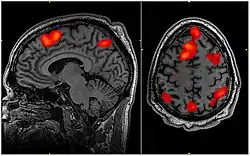

Durch den Einsatz moderner bildgebender Methoden, vor allem PET und fMRT, ist es möglich geworden, neuronale Vorgänge grob zu beobachten, die dem Prozess der Entscheidungsbildung zugeordnet werden können. Dabei deuten die bisherigen Ergebnisse darauf hin, dass manche Entscheidungen im Gehirn bereits getroffen werden, bevor die Person sich ihrer bewusst wird. Allerdings handelt es sich bei den Entscheidungen in diesen Experimenten bis dato um „folgenlose“ Spontanentscheidungen, z. B. welche Hand zum Greifen benutzt wird. Kritiker wenden deshalb ein, dass eine empfundene Freiheit der Entscheidung insofern doch real sein könnte, als die empfindende Person die Ausführung der Handlung steuern und überwachen könnte und in diesem Prozess die Möglichkeit hätte, die Aktion noch zu unterbrechen oder zu modifizieren. Dies wurde in dem Vorschlag ausgedrückt, die bewusst empfindende Person hätte möglicherweise eine Art „Vetorecht“. Spätere Experimente deuteten jedoch darauf hin, dass auch Veto-Entscheidungen unbewusst getroffen werden und erst nachträglich als freie Entscheidungen empfunden werden.[6]

Nach dem gegenwärtigen Erklärungsmodell der Hirnforschung über die Steuerung der Willkürmotorik haben viele, vor allem grundlegende, Antriebe für das Verhalten des Menschen einen subkortikalen Ursprung – sie entstehen im limbischen Bewertungs- und Gedächtnissystem. Dieses aktiviert die Basalganglien und das Kleinhirn, die wiederum die kortikalen Prozesse in Gang setzen. Dann erst setzt die Empfindung ein, etwas zu wollen. Damit stimmt überein, dass bei Willkürhandlungen zuerst in den Basalganglien und im Kleinhirn neuronale Aktivität auftritt und erst danach in der Großhirnrinde.